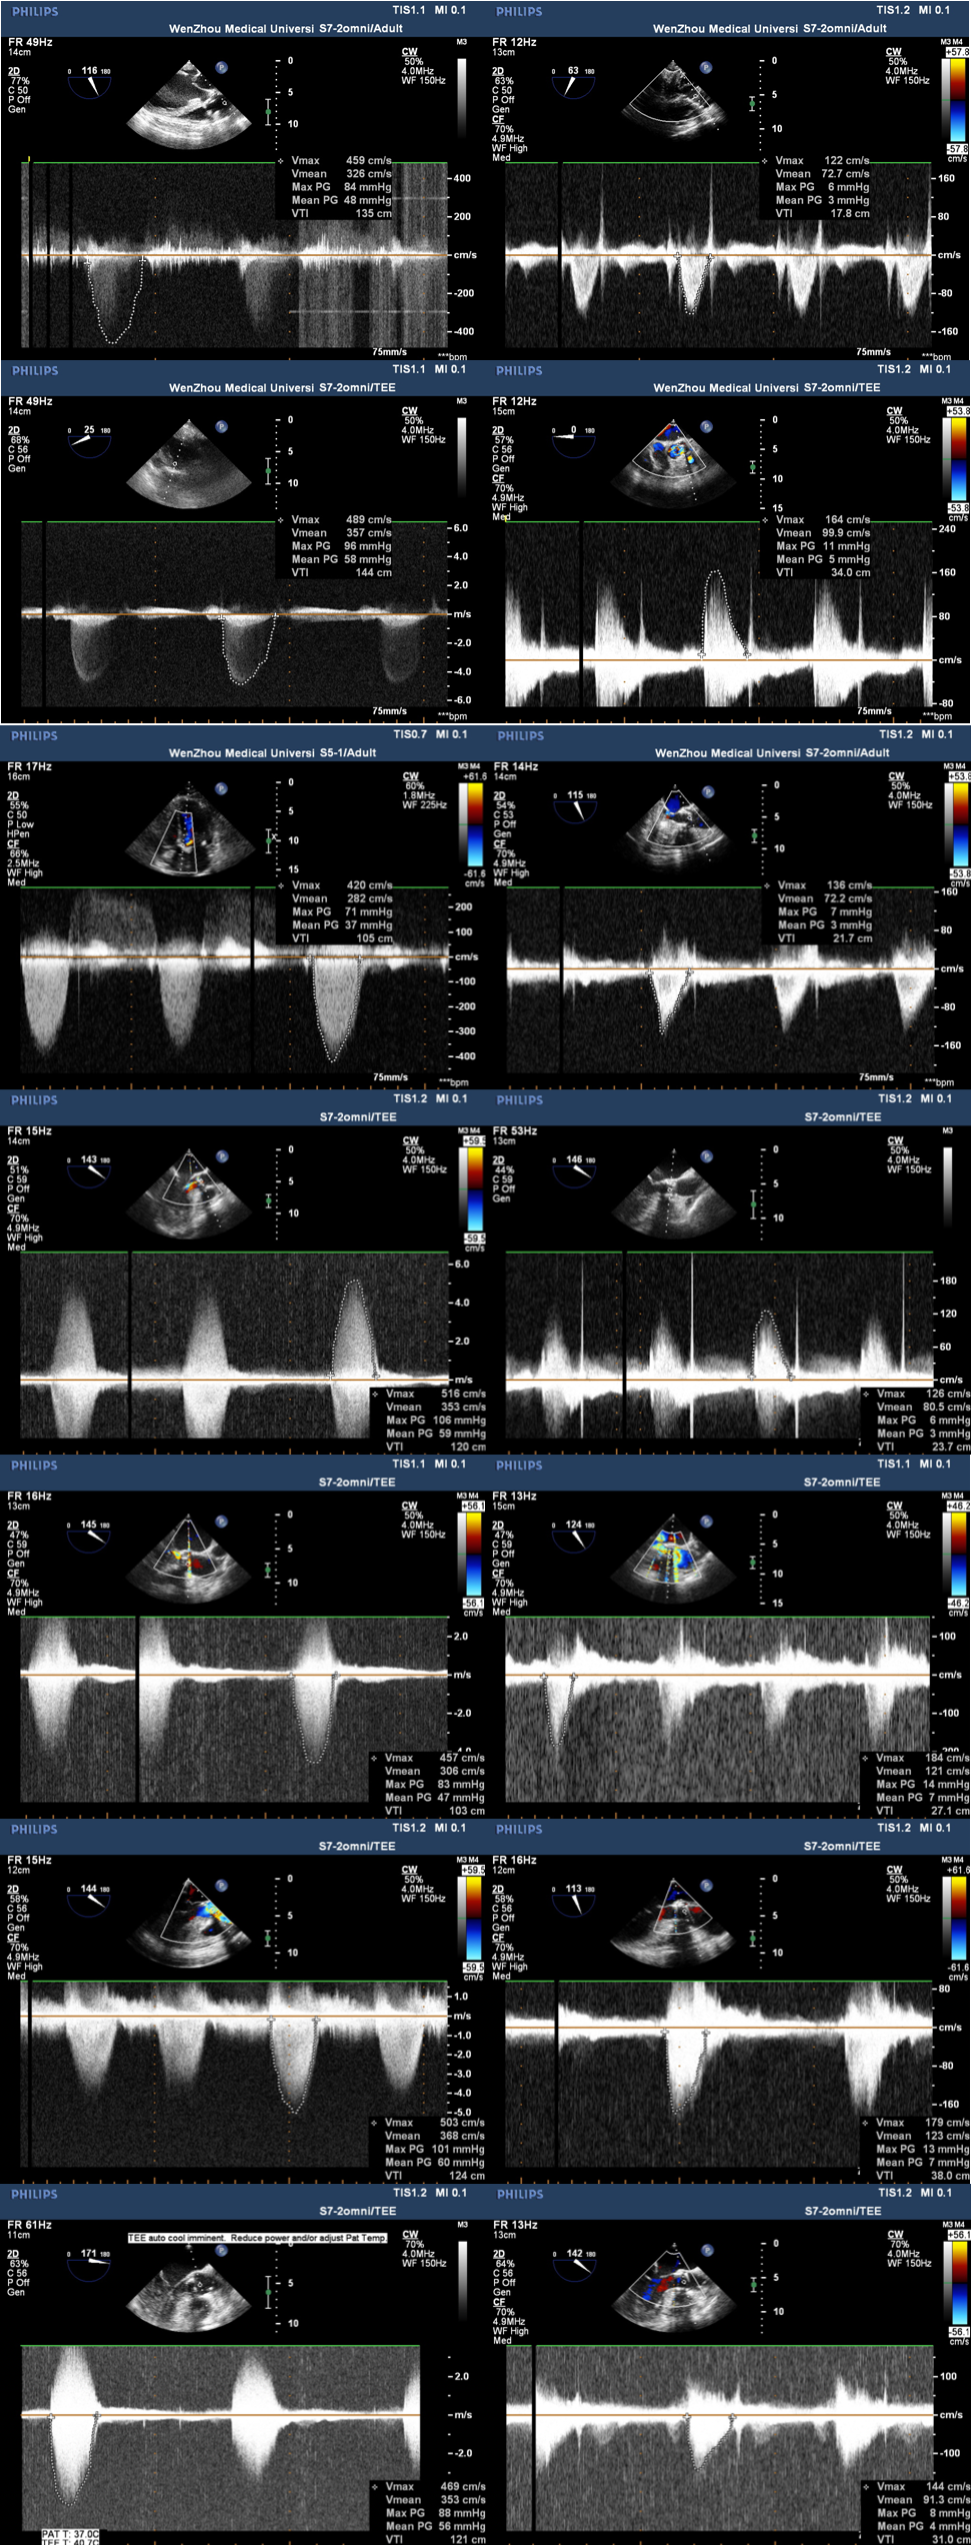

近期,温州医科大学附属第一医院心脏外科顺利完成由北京安贞医院牵头,联合国内多家知名心脏中心实施的佰仁医疗Renatus®球扩式介入主动脉瓣临床试验入组及手术任务。温州医科大学附属第一医院心脏外科作为浙南地区最早开展TAVI手术,并拥有最大手术量的科室,成为浙南唯一授权使用该介入瓣膜的单位。此次也交了一份满分答卷。所有7例接受该微创球扩瓣膜植入的患者,手术效果满意,无一例并发症,均无明显瓣周漏,无需术后安装起搏器。意味着温州医科大学附属第一医院心脏外科从2018年率先开展经导管主动脉瓣置换术(TAVR/TAVI)以来,又迈入一个新的台阶。

近日温州医科大学附属第一医院心脏外科连续完成了7例佰仁球扩TAVI瓣膜手术,术中心超及随访复查结果都非常满意,没有一例并发症,完美解决了患者瓣膜狭窄的问题。

如下图所示,取得了极其满意的效果。